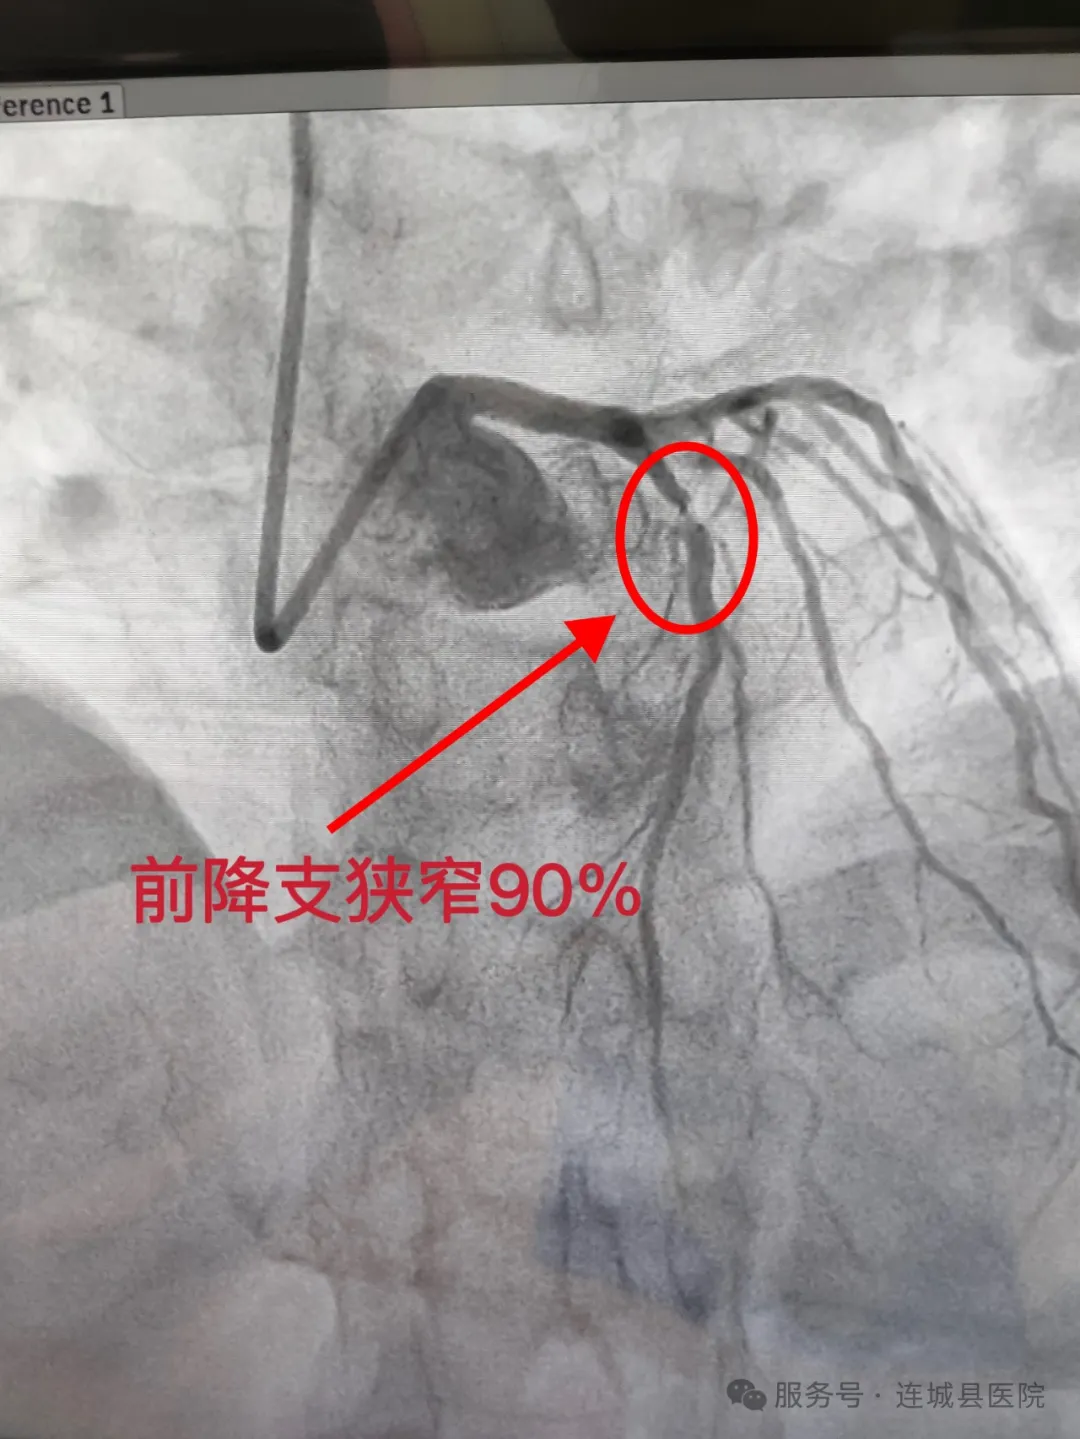

14时15分,铅衣战士们在导管室展开生死竞速。面对随时可能骤停的心脏,介入团队凭借毫米级操作精度,在错综复杂的血管网络中精准定位病变部位。当导丝穿越90%狭窄的前降支时,手术间响起第一声捷报。31分钟后,一个药物涂层支架完美植入,闭塞血管瞬间恢复血流,监护仪上跃动的正常波形宣告着这场“战役”的胜利。